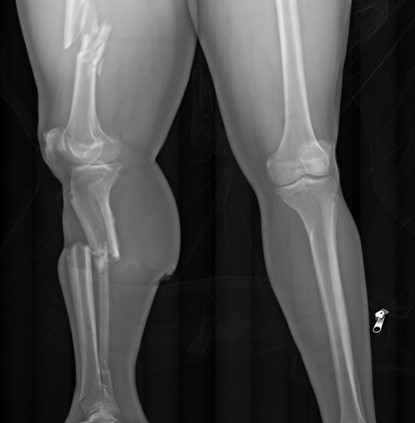

The second pathway by which we reach an undetermined manner is when extensive decomposition or other soft tissue loss (such as fire damage) interferes with our ability to determine a cause of death. Think of completely skeletal remains discovered in an abandoned building. Sometimes, indicators of potentially lethal injuries can still be identified – for example, a gunshot wound of the skull or knife marks on a rib. But, as the aphorism goes, “an absence of evidence isn’t necessarily evidence of absence” – a bullet or blade could be lethal while only striking soft tissue (especially in regions like the abdomen or neck). If we cannot rule out non-natural causes of death, the best choice for manner is “undetermined.”